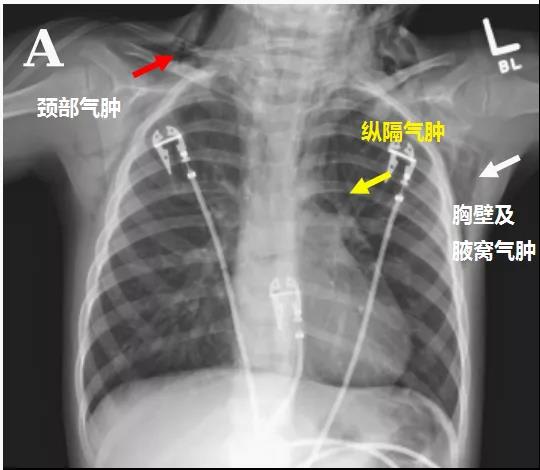

感冒、發(fā)熱、咳嗽,怎么辦?在中國,很多人都有一個習慣:吃點阿莫西林“消炎”!阿莫西林以前是非處方藥,一般還是比較安全的。然而,最近國外報道了一個奇怪的病例:3歲男孩口服阿莫西林之后竟然出現(xiàn)縱隔、心包氣腫,眼眶周圍積氣導致眼球突出!突然覺得,面對神奇的醫(yī)學,千奇百怪的疾病,我們還是too young!病例介紹

此次因疑診鏈球菌咽炎口服阿莫西林治療,口服第一劑后便出現(xiàn)雙側眼眶周圍腫脹、左眼不能睜開、喘息、低氧血癥、廣泛皮疹,遂來院就診。

無咳嗽、打噴嚏、劇烈嘔吐、劇烈體力活動或創(chuàng)傷史。隨后出現(xiàn)右側眼球突出,面部和頸部迅速腫脹,呼吸窘迫加重。

頭顱、胸部CT提示廣泛皮下氣腫、縱隔氣腫、心包積氣、甚至眼眶周圍都積氣,眼球突出!頸部無感染征象,腸管無破裂征象,看來氣體還是來自肺部。但是,肺部無感染、無肺大泡、無劇烈咳嗽,只有間質性肺氣腫。縱隔氣腫、皮下氣腫的治療,核心是根除病因,切開引流效果不像氣胸那么理想,而且縱隔切開引流還存在手術風險。找不到病因,如何是好?考慮患者是過敏體質,有皮疹,繼續(xù)呼吸機輔助呼吸,先治療過敏,肌肉注射腎上腺素、靜脈注射類固醇激素和抗組胺藥、吸入支氣管擴張劑等。經上述治療,臨床表現(xiàn)和影像學方面都有迅速的改善。隨后拔出氣管導管,口服類固醇激素出院,門診隨訪。